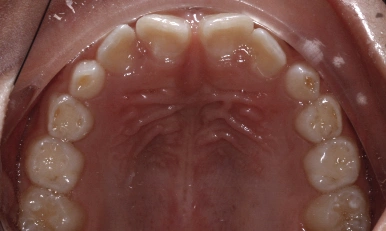

Patient Results